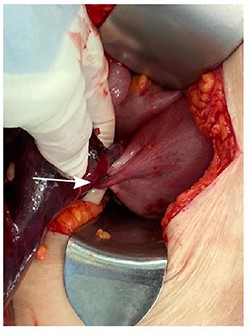

A diagnosis of right ovarian torsion was made and the patient underwent exploratory laparotomy, right salpingo-oophorectomy with intra-operative frozen section and omentectomy. Intra-operatively, torsion of right gonadal vessels was noted (Fig. 2). The right gonadal vessels were taken between ties. The right fallopian tube was ligated. Frozen section from the right salpingo-oophorectomy showed features of benign serous cystadenoma with extensive haemorrhagic infarction in keeping with torsion. There was no evidence of malignant cells. Omentectomy was performed and sent for frozen section, which returned with no evidence of malignancy. The abdominal cavity was washed thoroughly and closed with sutures.